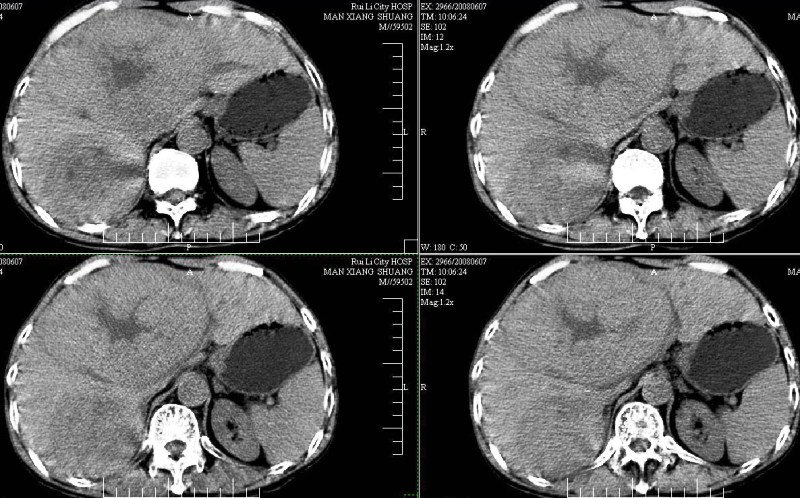

标题: CT13937:M,42A.腰疼一周。

ct(椎间盘扫描):椎间盘炎,建议dr。

dr:l4骨质破坏,转移可能。

胸部摄片未见异常。临床医生体检发现上腹部饱满。

ct:肝癌腰椎转移。临床医生:肝脏、骨转移,肿瘤来自?前列腺?!